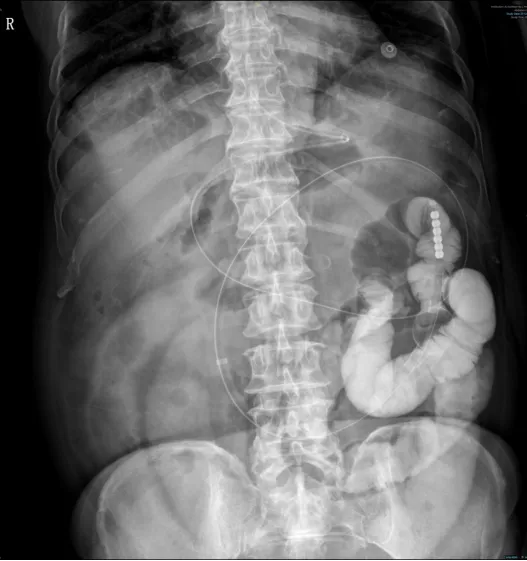

84岁的陈先生连续食用多个柿子加上粘糕之类的食物后,因腹痛腹胀伴恶心呕吐4天,并自觉停止排气、排便,来昆山市一医院就诊。

急诊外科接诊后,快速安排急诊CT等相关检查确诊粪石性小肠梗阻,将其收治入院,入院后置鼻胃管引流效果不佳,考虑到陈先生年龄和身体状况的因素,手术风险大,急诊外科副主任刘刚医疗团队讨论后为其进行个体化治疗方案——DSA引导下经鼻肠梗阻导管置入术,术后陈先生腹胀症状迅速缓解,并排出了球样的粪石。很快陈先生就可以正常进食,陈先生和家人非常满意,出院后亲自到门诊送锦旗感谢医务人员。

无独有偶,70多岁的吴女士因中上腹疼痛11小时来院就医,发病前同样进食了较多柿子,出现中上腹的剧烈疼痛伴频繁的呕吐,并自觉排气、排便减少。吴女士入院后,确诊为粪石性肠梗阻,予以置胃管减压后,腹痛迅速缓解,并很快解出粪石样大便,后康复出院。

急诊外科常规开展经鼻肠梗阻导管置入术,术后患者胃肠道水肿明显消退,腹胀、腹痛减轻,肠道功能恢复的更快,能够及时缓解患者肠梗阻的症状,为肠梗阻患者提供了更优质的治疗。